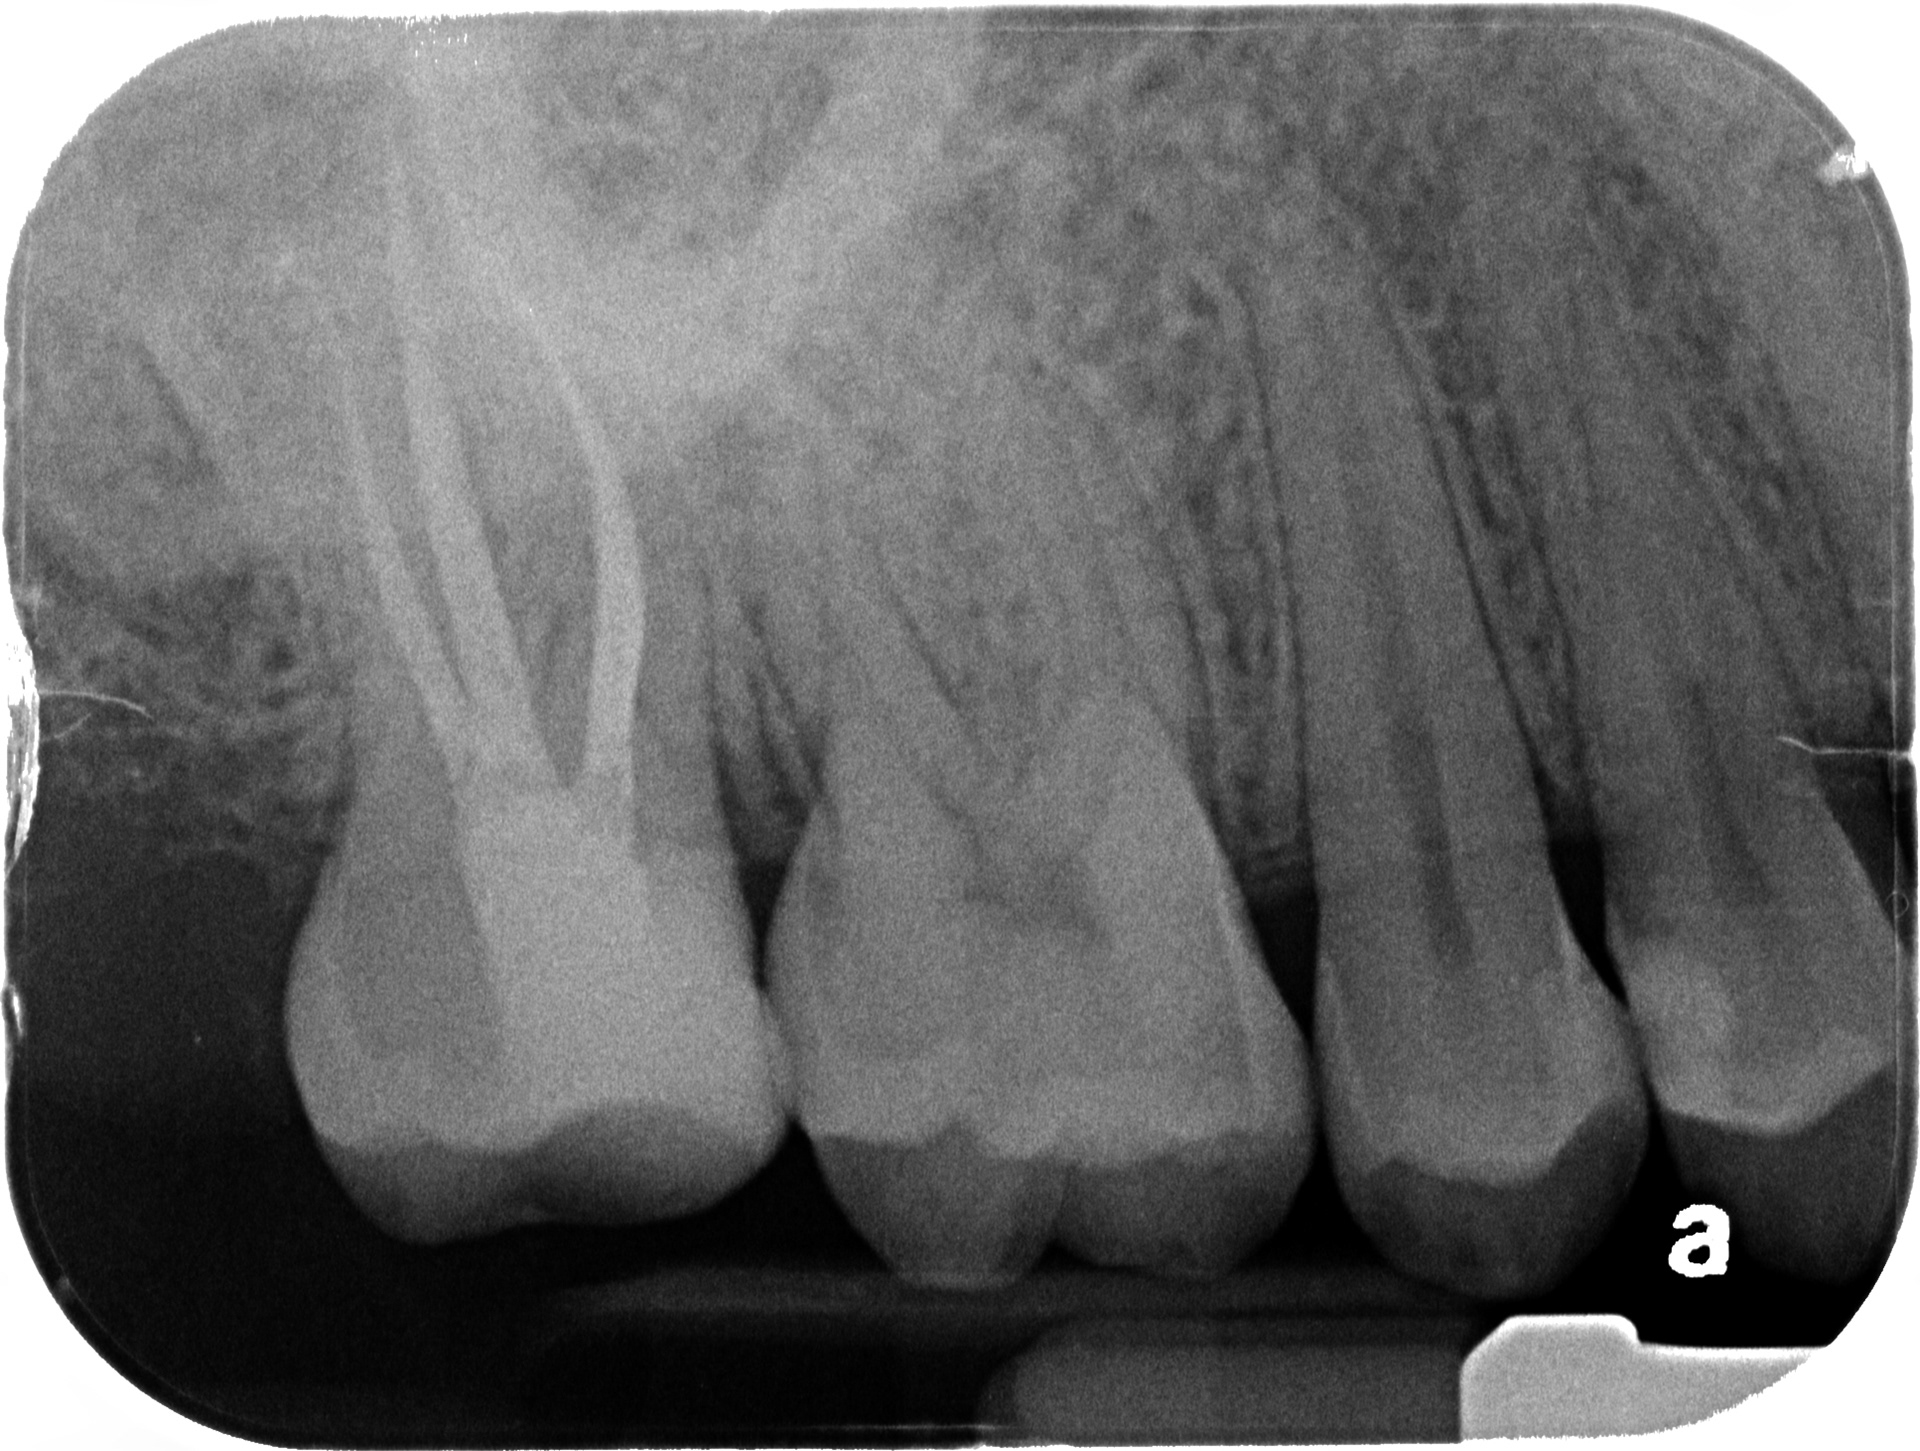

47

INITIAL

WORKING LENGTH

FINAL